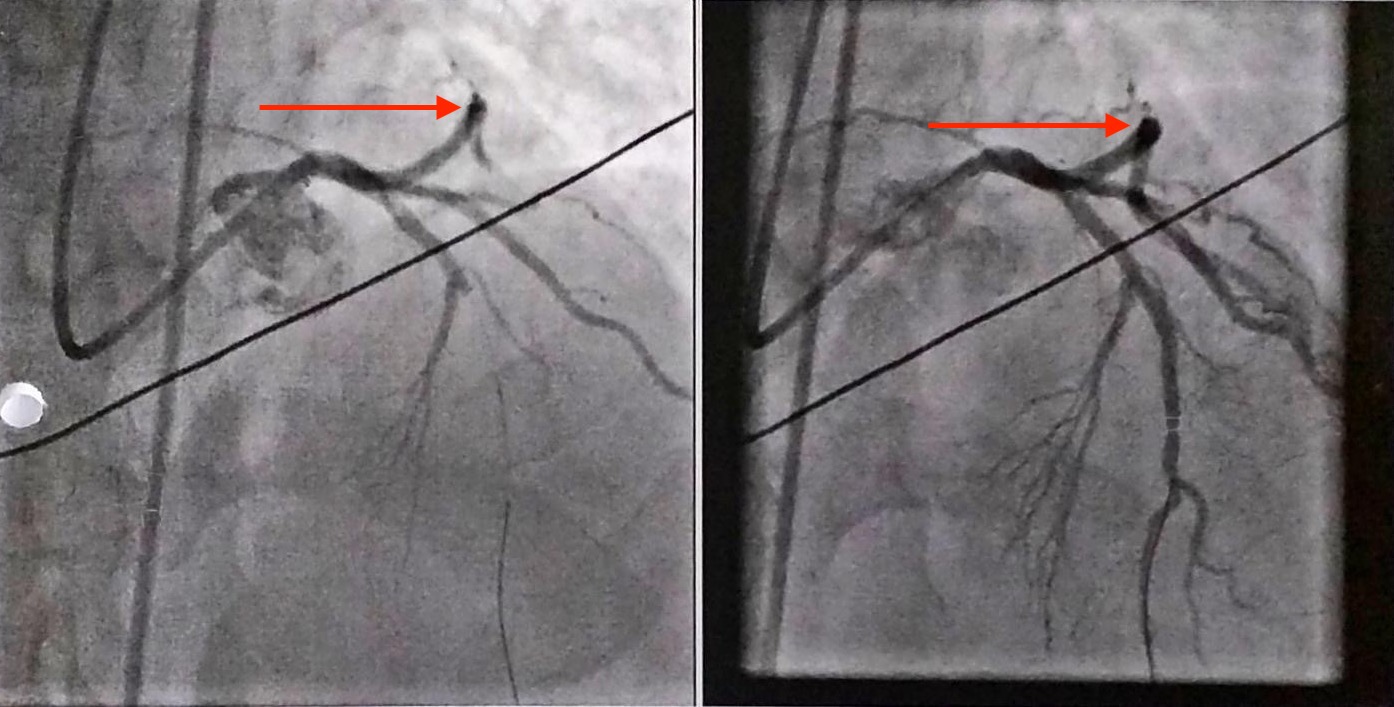

An electrocardiogram revealed ST segment elevation in leads 1, AvL, and V2 to V5 and peaked T waves in leads V2 to V4, indicating anterolateral ST-elevation myocardial infarction. A coronary angiography was then performed, results of which revealed occlusion of the posterior mid-left anterior descending coronary artery (Figure 2). A bare metal stent was placed at the occlusion. Door-to-balloon time was 78 minutes.